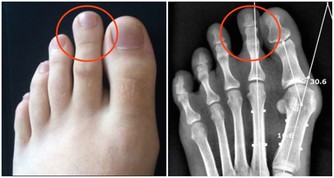

4、激素分泌失調。

腦下垂體生長動情激素、內分泌失調、心理神經敏感、易怒、不自信、多疑,頸椎變形,

會造成腰椎變形,腰椎變形會壓迫坐骨神經,坐骨神經會壓迫附盆腔,

同時引發內分泌失調:腰酸背痛,腿腳無力,易疲勞,內分泌失調,月經不調,痛經,易肥胖,婦科感染,性生活失調,宮頸糜爛,子宮肌瘤等等。